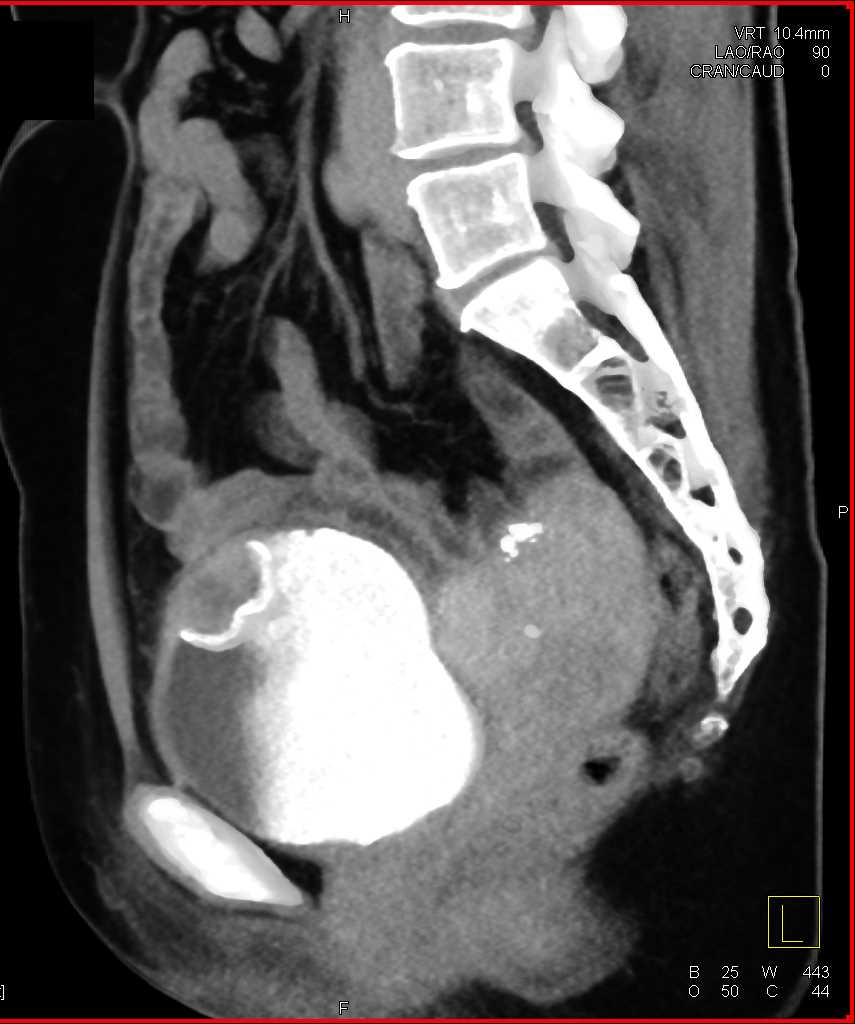

Urachal Carcinoma of the Bladder